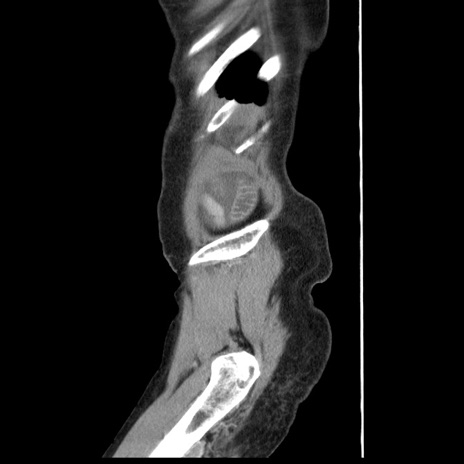

冠状断像

【症例】80歳代女性

【主訴】腹痛

【現病歴】8時間前から腹痛あり来院。

【既往歴】糖尿病、脂質異常症、子宮体癌にて子宮全摘術

【身体所見】意識清明・会話良好だが腹痛で苦悶様、全腹部にわたって反跳痛と圧痛あり

【データ】WBC 13600、CRP 0.14、LDH 224、CK 90